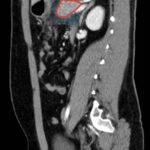

Computed tomography of the abdomen and pelvis with contrast show edema of the pancreas (red outline) and duodenum (yellow arrow) with peripancreatic inflammation, fluid and fat stranding (blue highlight). The distal pancreatic tail was noted to appear normal (green arrow). There was no organized drainable fluid collection, and no parenchymal hypo-enhancement. These findings are consistent with moderate severity acute interstitial pancreatitis.